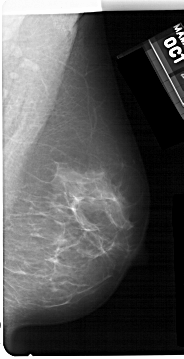

A_1477_1.LEFT_MLO

LEFT_MLO LINES 5491 PIXELS_PER_LINE 2881 BITS_PER_PIXEL 12 RESOLUTION 43.5 OVERLAY